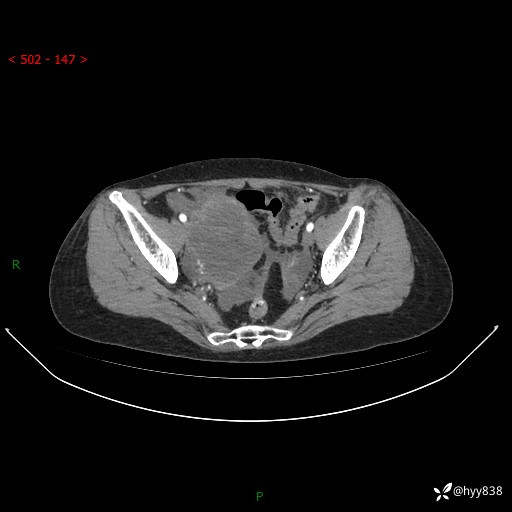

老年女性,尿频2月。超声发现盆腔囊实性占位,CT能否明确诊断---结果公布

现病史:患者绝经3-4年,期间无阴道出血及排液。患者近2月感尿频,自行口服中药治疗,症状无明显缓解。2024-4-25日于我院门诊就诊,行阴道彩超示:子宫肌瘤(大小约12*10mm,后壁),子宫右前方囊实性占位性病变(大小约126*82mm肿块声像,边界尚清,以无回声为主,可见范围约84*27mm稍高回声),内膜3mm。建议手术治疗。门诊以“卵巢囊肿”收入院。 病程中精神、食欲、睡眠可,大小便正常,体重体力无明显变化。

腹盆CT平扫

增强